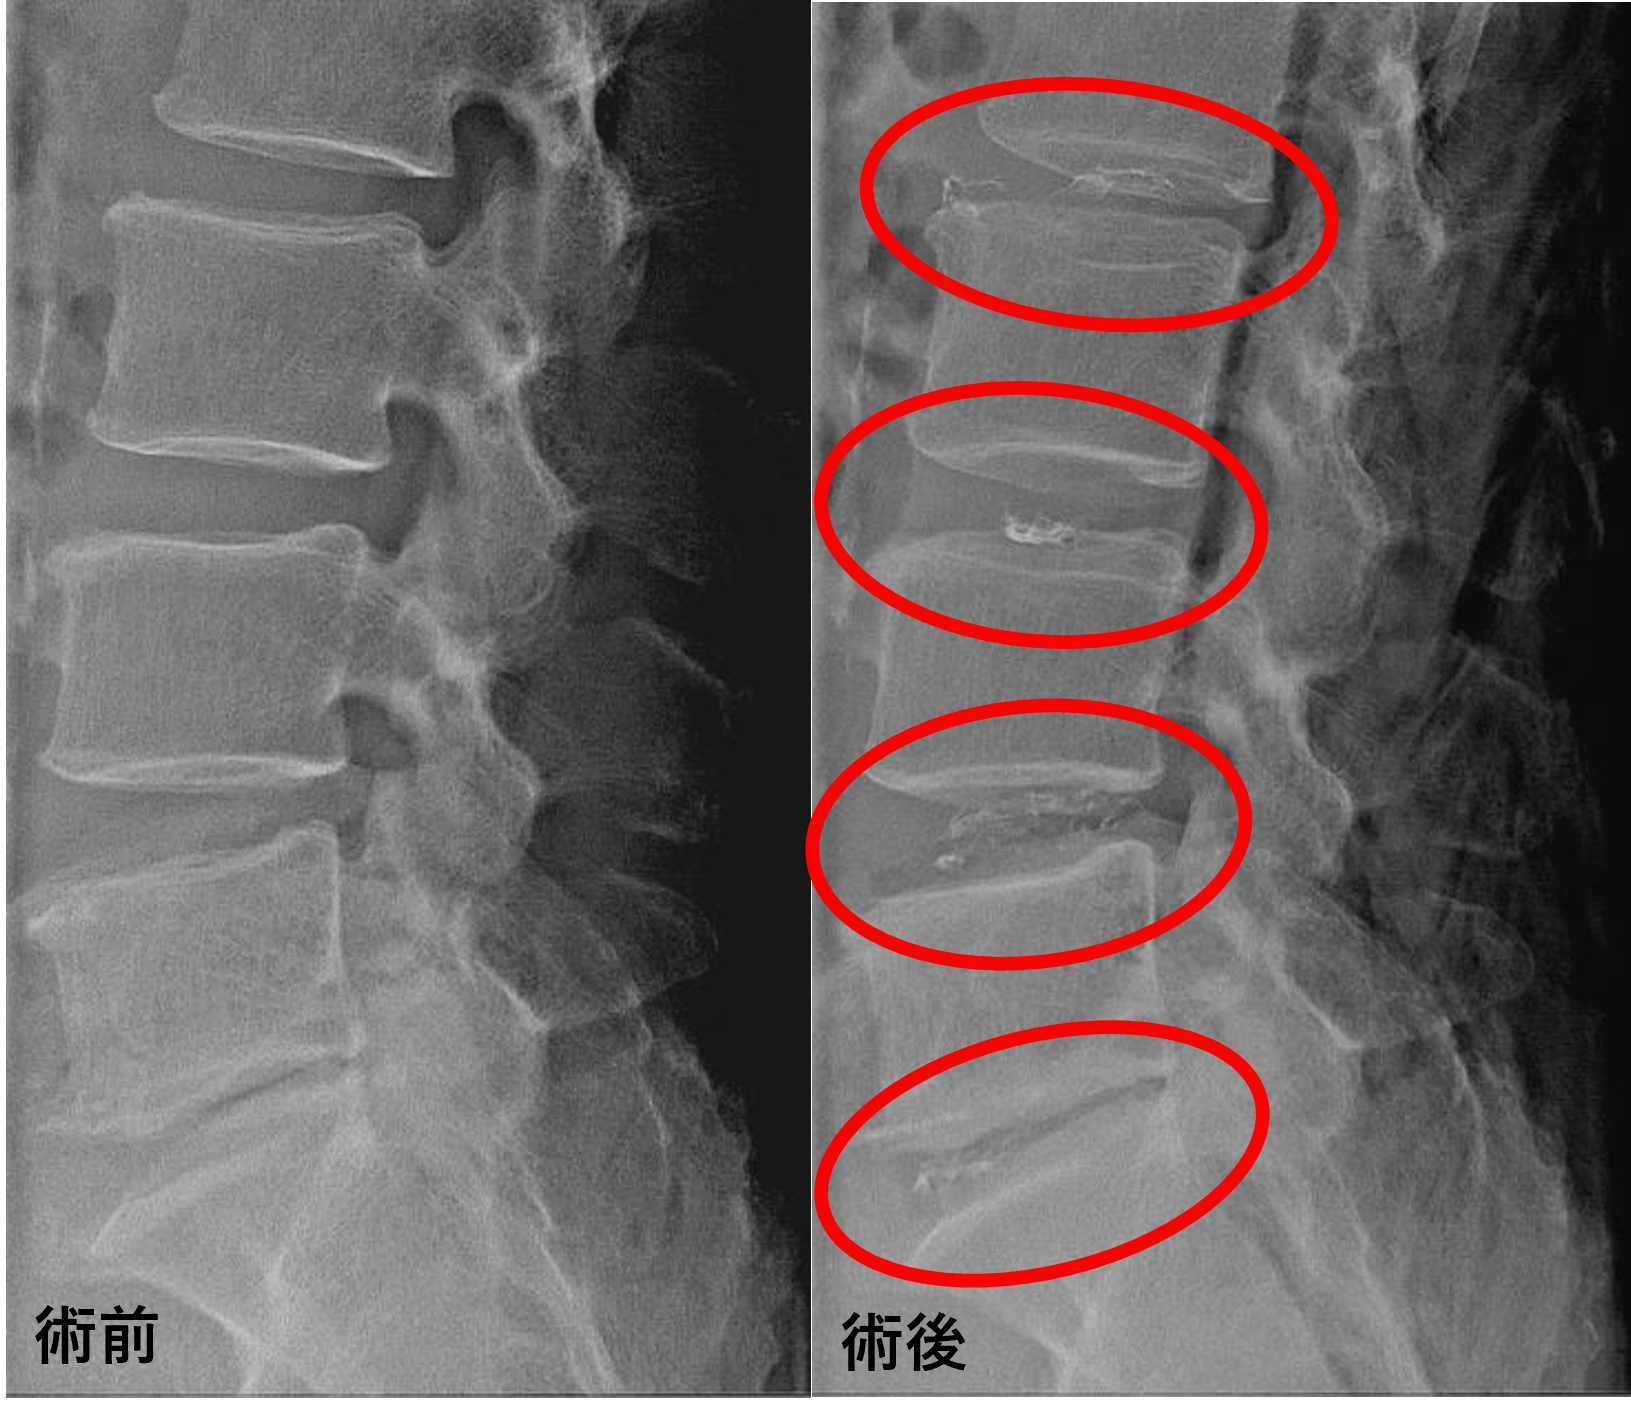

画像及び所見について

- L2/3、3/4、5/s – 椎間板変性

- L4/5 – 椎間板変性、椎間板ヘルニア

以上のことが画像上認められました。

L2/3、3/4、4/5、5/sの椎間板所見による脊柱管の圧排が、症状の原因の可能性が高い。

患者様と相談の元、L2/3、3/4、4/5、5/sにセルゲル法を施行